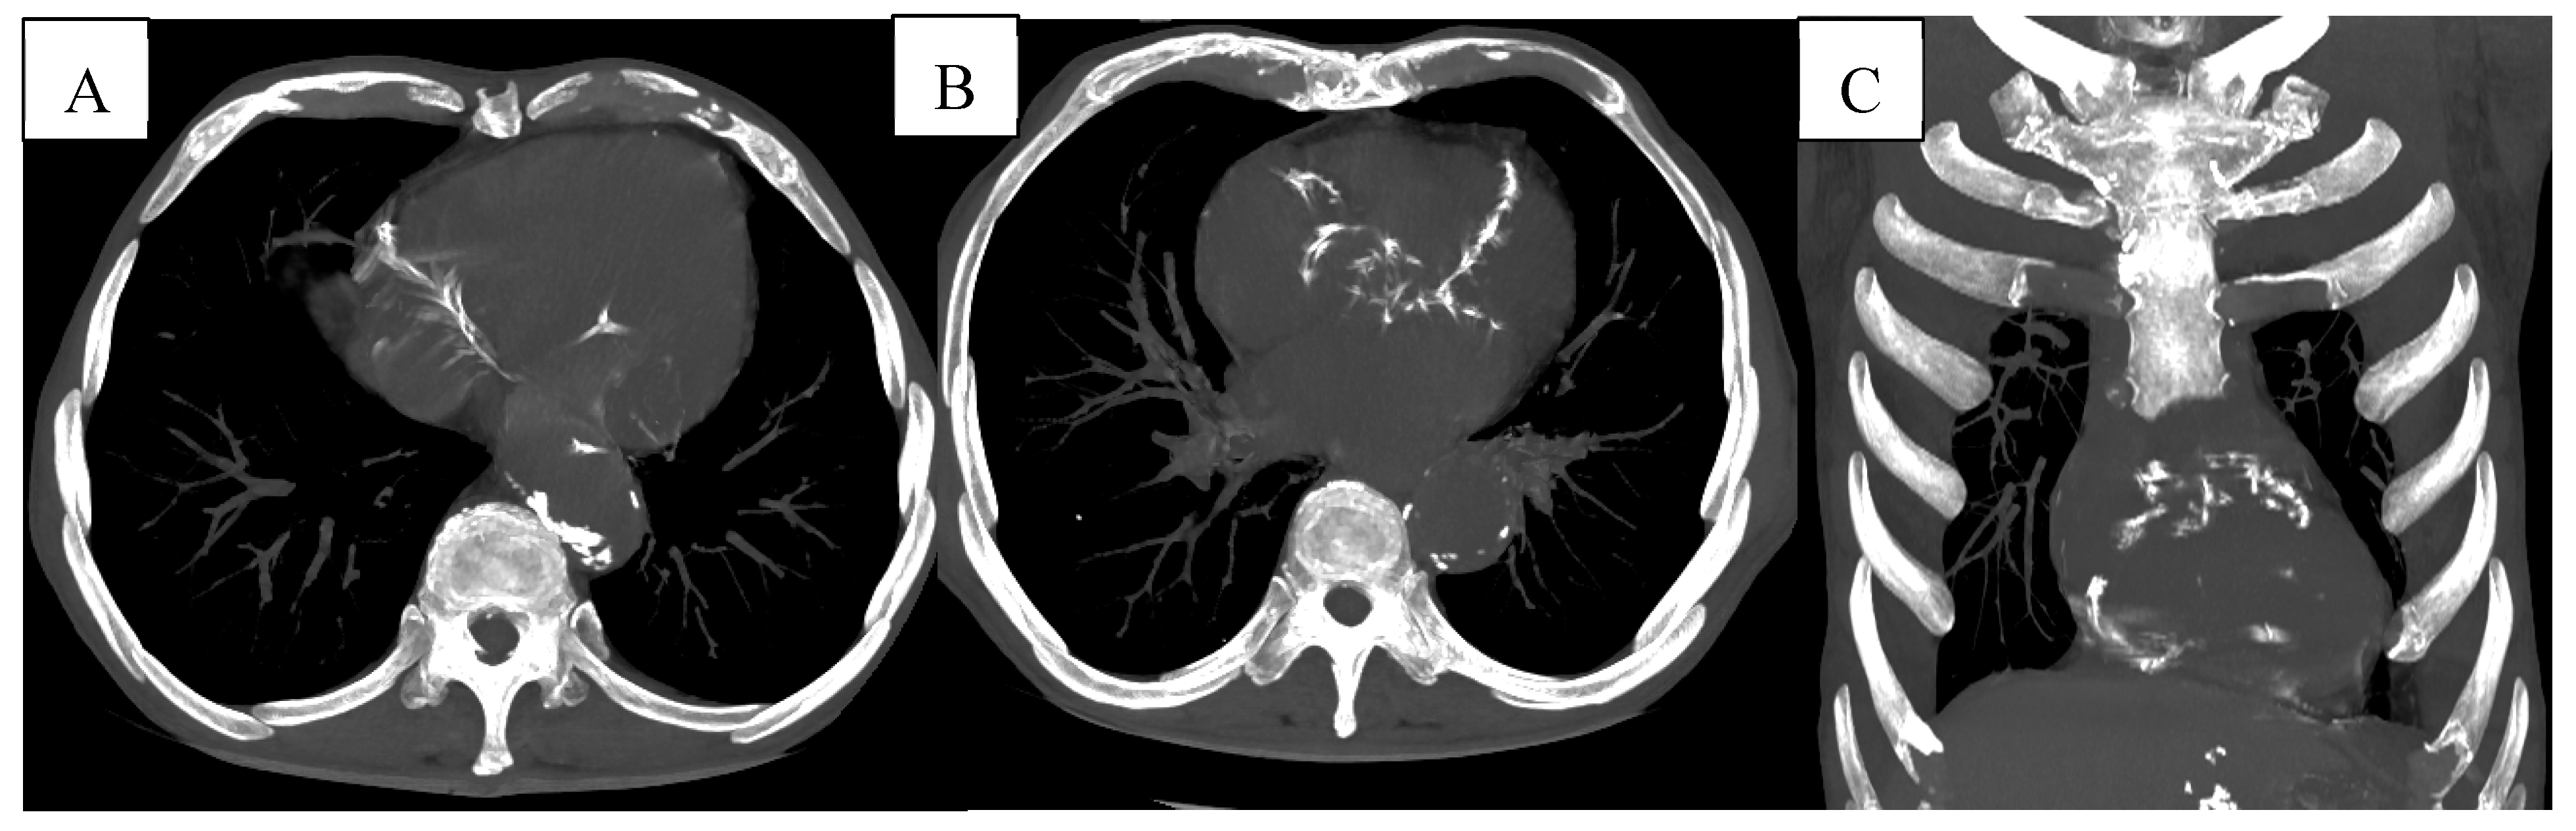

Further CT examples of infectious and vascular comorbidities are presented in Figure 7.

Advanced pulmonary vascular changes and cardiovascular calcifications were observed on CT, as illustrated in Figure 9.

Figure 7. (A) Pneumonia- Pulmonary consolidation in the lower lobe of the right lung, with the presence of air bronchogram. (B) Pulmonary infarction represented by the peripheral wedge-shaped pulmonary consolidation in the right lung with its base towards the pleura.

Figure 9. (A-B) Multiple vascular calcifications of the thoracic aorta and proximal coronary arteries are visible, suggesting underlying atherosclerotic cardiovascular disease. (C) Coronal reconstruction further highlighting the presence of extensive aortic and coronary calcifications.